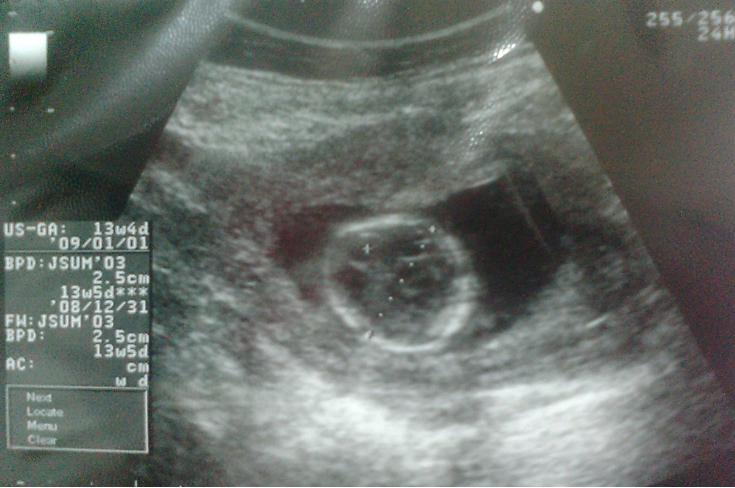

先生が測定のために頭の断面を見せた時。。。

息子が一言

『お母さん、赤ちゃんの頭玉子みたい!!』とw

発想にびっくりでしたw

そうとう印象深かったのか、今日はこればかり言っていました